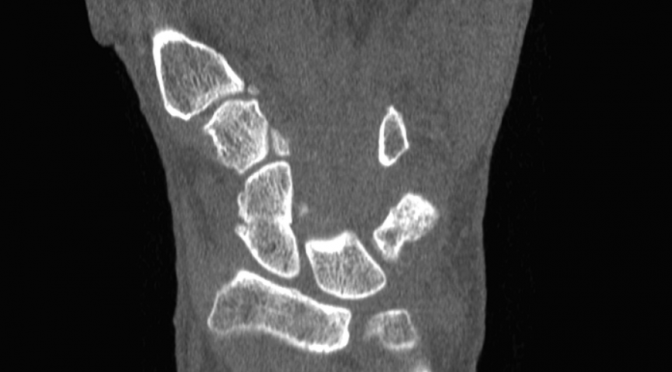

CT assessment of patients casted for a non-displaced scaphoid fracture shows union occurring at approximately 7.5 weeks, with a majority of fractures healing in less than 6 weeks, according to a 2016 study by Ruby Grewal et al. Similar studies using plain X-Ray demonstrated union time to be anywhere between 10 – 24 weeks. The authors noted the union time on CT may even be overestimated because the majority of patients’ first CT scan after casting was not until 6 weeks.

In a previous study, Professor Timothy Davis wrote CT studies demonstrate healing of a non-displaced fracture treated with a plaster cast can occur in as little as 4 weeks. If a fracture is displaced less than 2 mm, Davis said those CT studies suggest a plaster cast for 8 – 12 weeks.

CT is ideally performed for all scaphoid waist fractures in the first week after injury to classify whether they are displaced or non-displaced, said Professor Davis, an orthopedic surgeon at Woodthorpe Hospital in Nottingham, UK said in his research paper.

By using CT as a baseline, researchers at the Roth/McFarlane Hand and Upper Limb Center in London said they were able to identify fractures which may have appeared non-displaced on X-Ray, but were actually minimally displaced.

“We feel that the added visualization of CT over plain radiography enables the surgeon to properly select which fractures are appropriate for non-operative cast treatment with an expected high degree of union,” the researchers said in a study published in The Open Orthopaedics Journal.

Fifteen percent of acute fractures of the scaphoid waist fail to unite if treated non-operatively in plaster, resulting in a persistent loss of function, according to the 2013 article. Plain X-Rays do not clearly show fracture features such as displacement and communition. Previous inter-observer studies have shown radiographs of scaphoid fractures are neither sensitive nor specific.